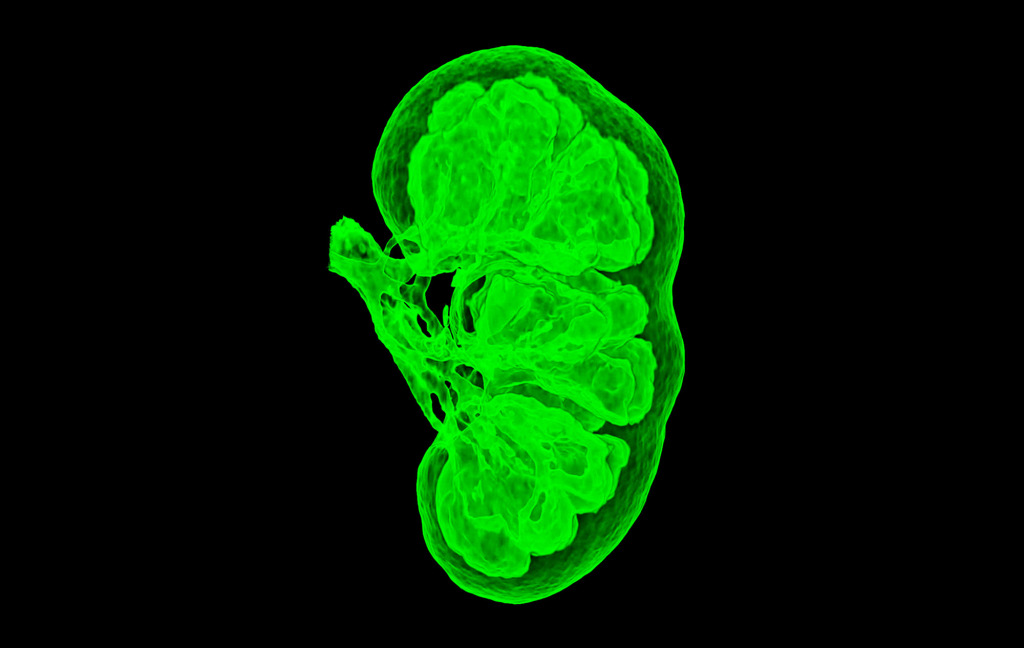

My favourite image is a 3D CT scan of lung airways.

It was one of my first images using a completely redesigned tissue density colour table. Green is the most dense tissue (bone) and purple is the least dense tissue (lung).

Combining these colours resulted in an extremely bright artistic image.